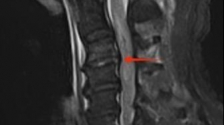

颈椎骨折伴颈脊髓损伤具有高致残、高致死的风险,不仅严重伤害了患者身心健康,亦为家庭带来沉重负担...